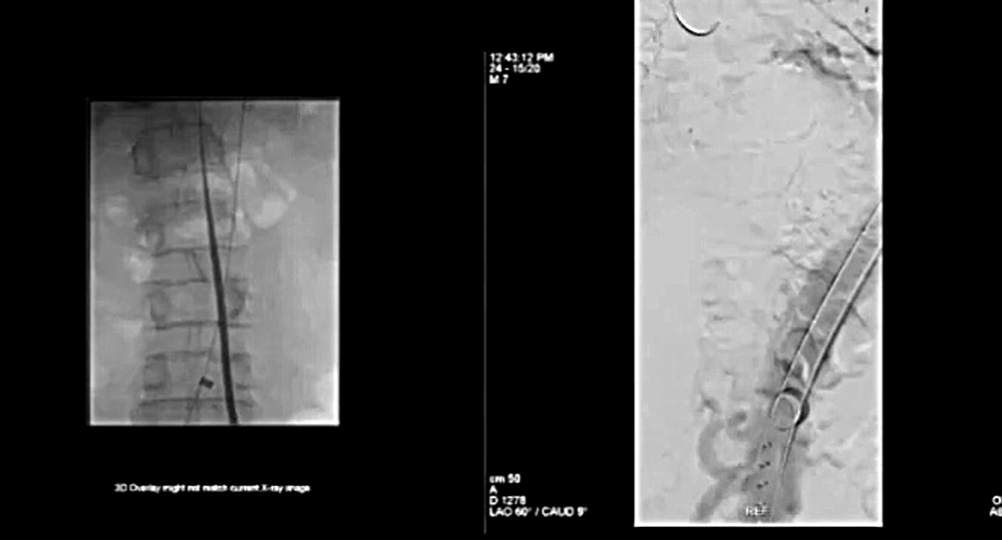

Cheese Wire

Cheese Wire技术为:通过从真假腔破口中穿过.014导丝,并向远端轻轻牵拉,纵向撕裂内膜来恢复真腔。

腔内电灼术不再拉线,而是直接将导丝通电,通过下图看到,可以通过一些导管来保护导丝,以便使内膜片处唯一暴露的导丝打折点通电。在内膜片处切开3cm的切口,然后在IVUS指导下回撤。

针刺破膜和连续的球囊扩张

针刺破膜和连续的球囊扩张其根本上仍然是从真腔进入假腔,使用大球囊使其破裂。